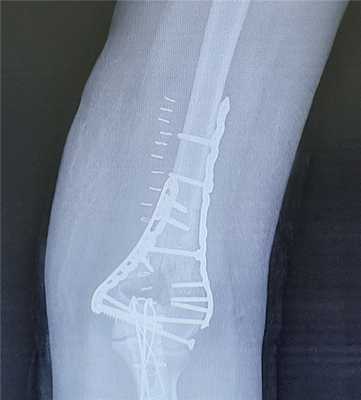

Ещё один клинический пример остеосинтеза тяжёлого перелома мыщелков плеча с использованием пластин с угловой стабильностью Synthes.

Пациентка Х, 54 лет, получила внутрисуставной Y-образный перелом мыщелков плеча. Смещение костных отломков настолько значительно, что диафиз плечевой кости близок к тому чтобы перфорировать кожу.

В случае настолько грубого смещения при первичном осмотре целесообразно выполнить анестезию перелома и устранить смещение с фиксацией конечности в задней гипсовой лонгтеной повязке. После обследования и предоперационной подготовки пациентка взята в операционную. Выполнен остеосинтез при помощи пластин с угловой стабильностью Synthes.

Послеоперационные рентгенограммы показывают, что смещение отломков полностью устранено, нормальные взаимоотношения костей верхней конечности восстановлены.